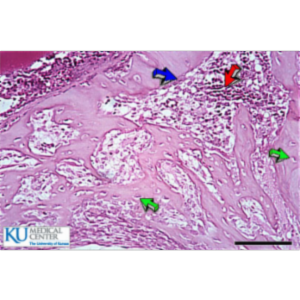

Bone Histology

Several images from histological preparations of bone can be viewed at this site.